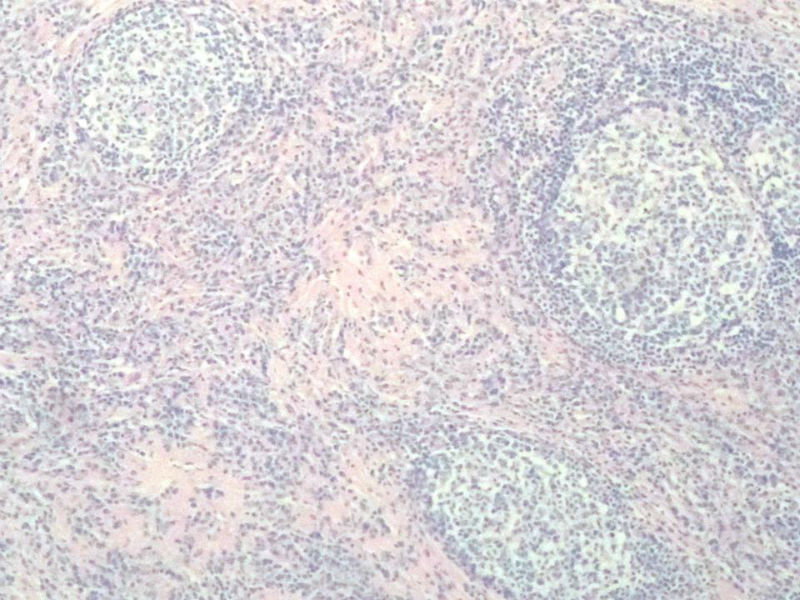

女,56岁,右颌下肿块两月余,检查肿块活动度差,手术切除。肉眼,灰白类圆形肿物,2X2X1厘米。包膜不完整,切面灰白色,质软。